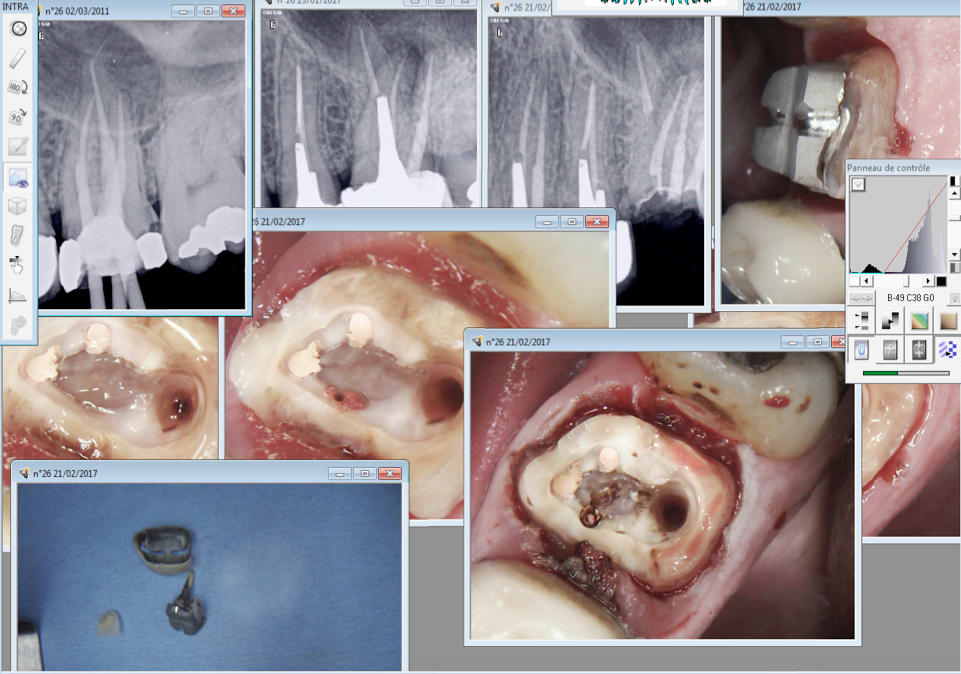

IC coiffe en 2006 sur cette 36, RTE que du distal. 2017 pÚche dans les mésiaux RTE de tous les canaux empreinte.

Je suis assez satisfait c'est propre au niveau paro, meme aprÚs séance de barbecue en 2006. -)

En 2006 avec les pro tapers c'était moyen moyen. Avec le réciproc R25 blue ca rentre comme dans du beurre. C'est pas compliqué c'est comme une bio sans l'anesthésie.

L'inlay core a dégagé en 5 secondes au coronaflex.

C'est pas la pulpe. Je suis content de ma "fidélisation" surtout quand j'arrive à trouver le MV2 6 ans aprÚs. Comme ca on passe 2 couches de peinture. -)

C'est la pulpe, c'est la pulpe.

Pas de réponse au froid. Curieux non ? -)))

C'est la pulpe c'est la pulpe.

Festival aujourd'hui ! -)))

jolie fĂȘlure, qui descend jusqu'au plancher en Ml et pas en distal, je fais quoi?

Perso, reconts collée et CR sans garanti.

Moi je fais un ic coiffe sans garantie. Hasta la vista baby. -)